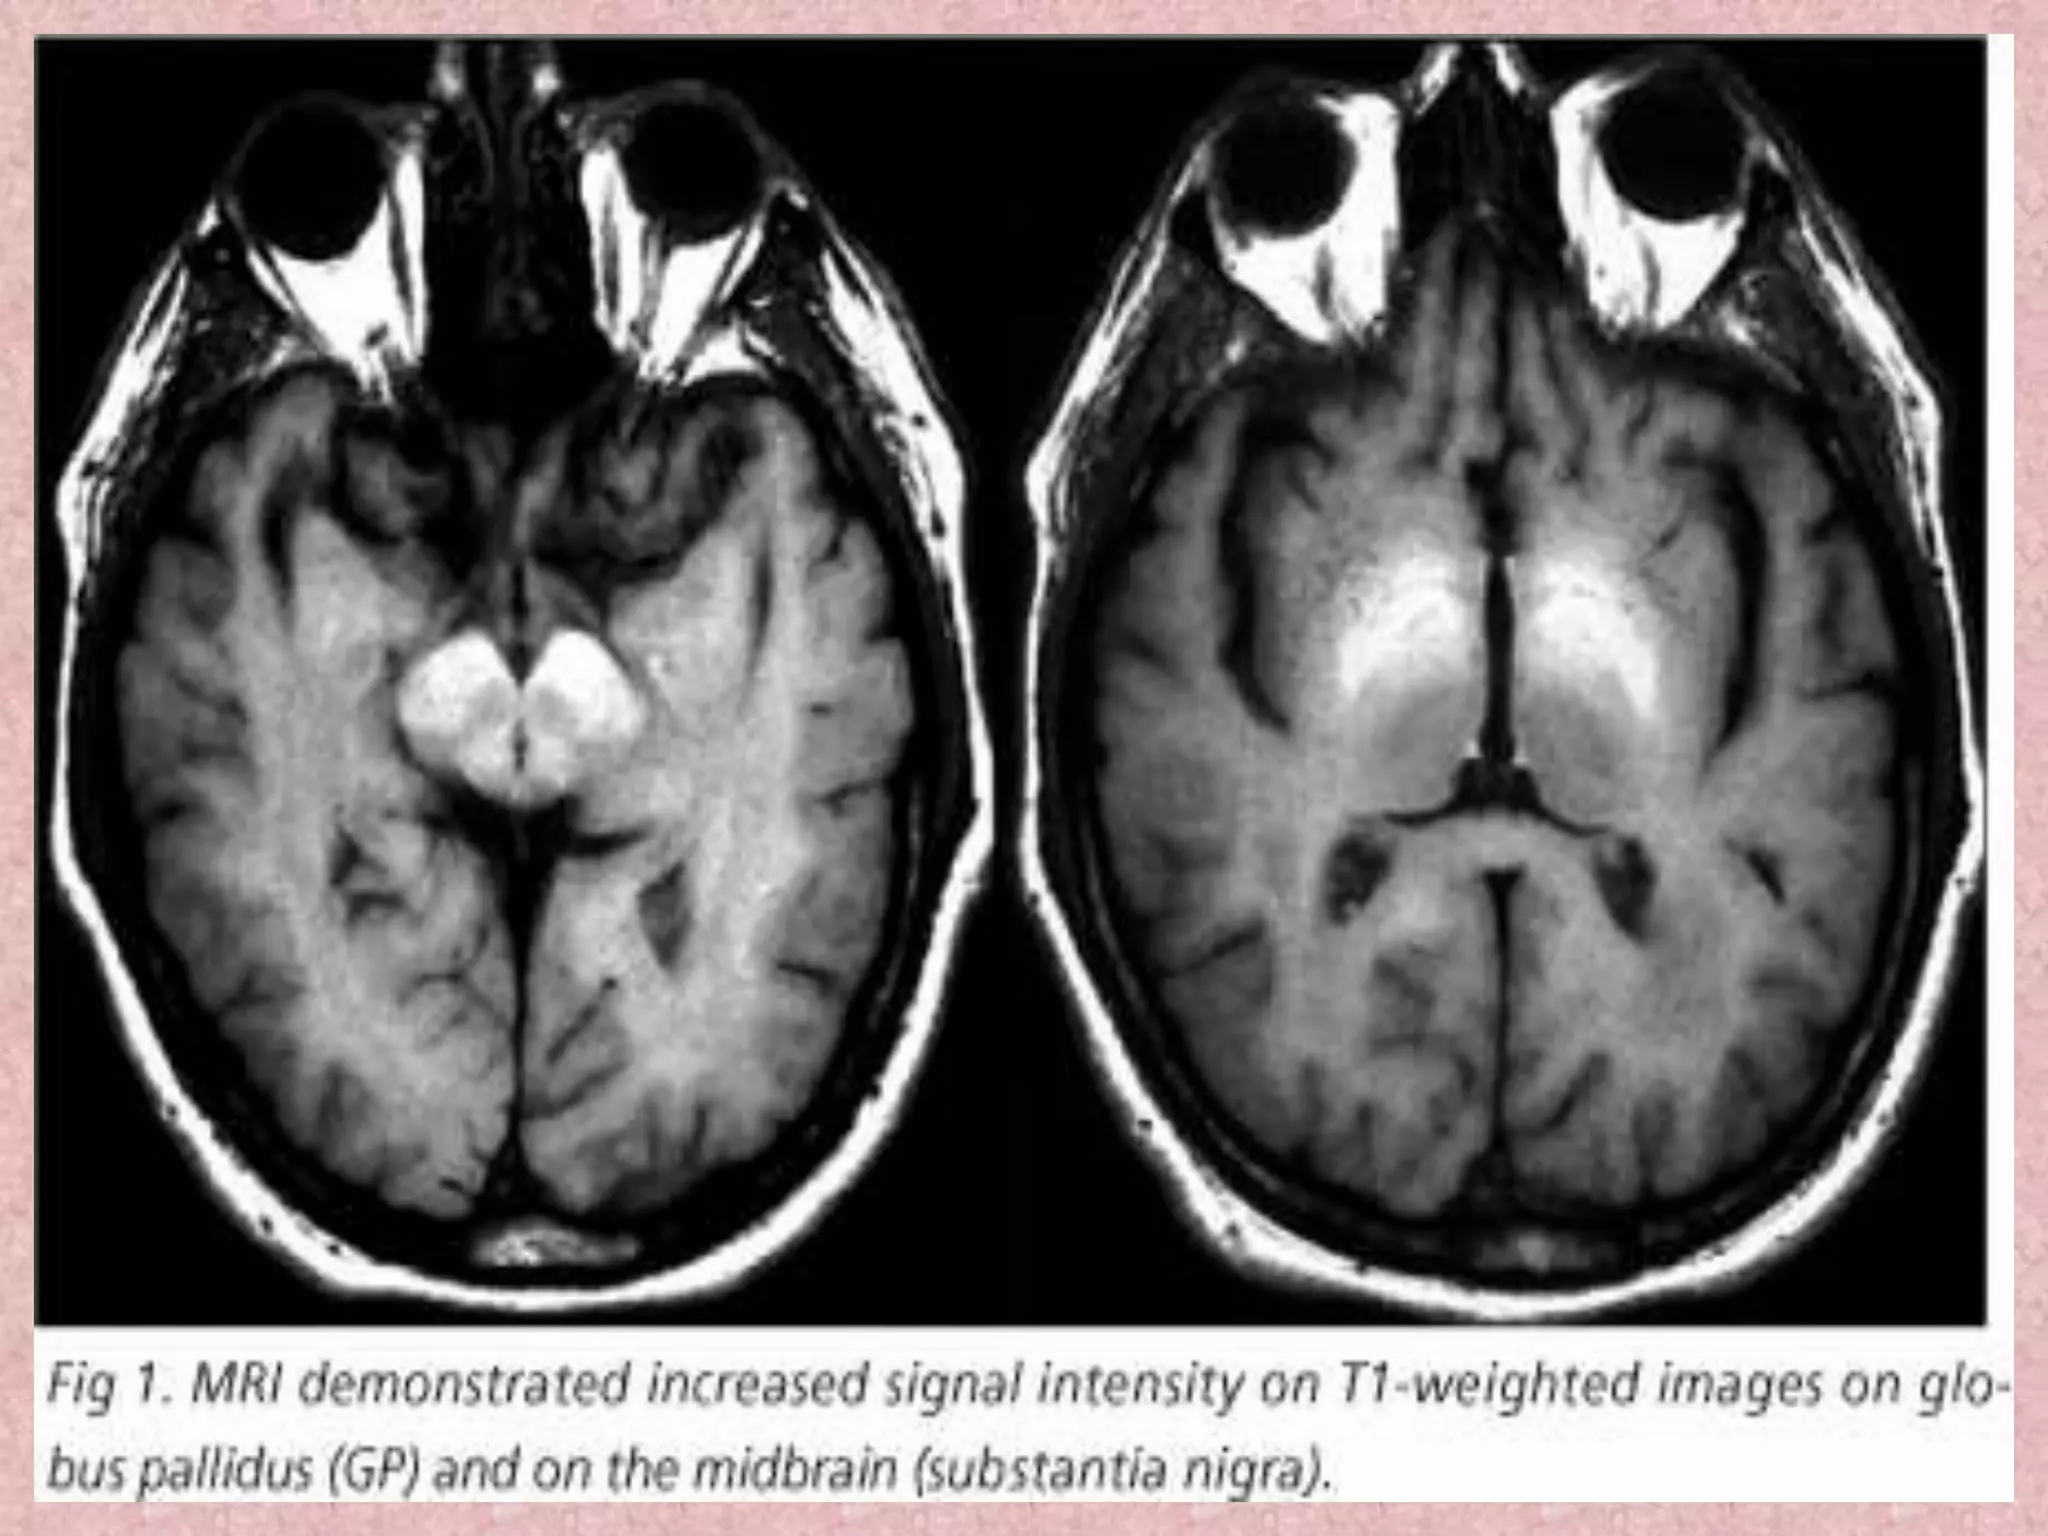

T1-weighted MR images show bilateral and symmetrical hyperintensities in the

substantia nigra and cerebral peduncle (A), subthalamic region and hemispheric

white matter (B), and the globus pallidus and putamen (C) in reversal

parkinsonism patient following embolization of intra-hepatic venous shunt.

T1-weighted MR imagesshow bilateral and symmetrical hyperintensities in the substantia nigra and cerebral peduncle (A), subthalamic region and hemispheric white matter (B), and the globus pallidus and putamen (C) in reversal parkinsonism patient following embolization of intra-hepatic venous shunt.